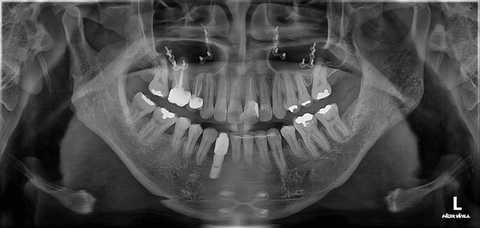

목어깨 턱관절 이명 삼차신경통 등 교근신경차단술 (교근축소술)로 고친다는 치과

치과인데 교근을 레이저로 태워서 신경을 끊는 끔찍한 시술 이거 하나밖에 안함

문제는 이 교근신경이 끊겨서 사용을 못하게되면 측두근이나 다른근육이 개입하게 되어 더심한문제를 일으킨다고 하는데요

저는 현재 짝턱으로 시술이 성공한 왼쪽턱에서 입만 벌리면 딱딱 소리가 나며

염증이 생겨서 일상생활이 불가하여

계획에도 없는 양악수술까지 하게 되었습니다